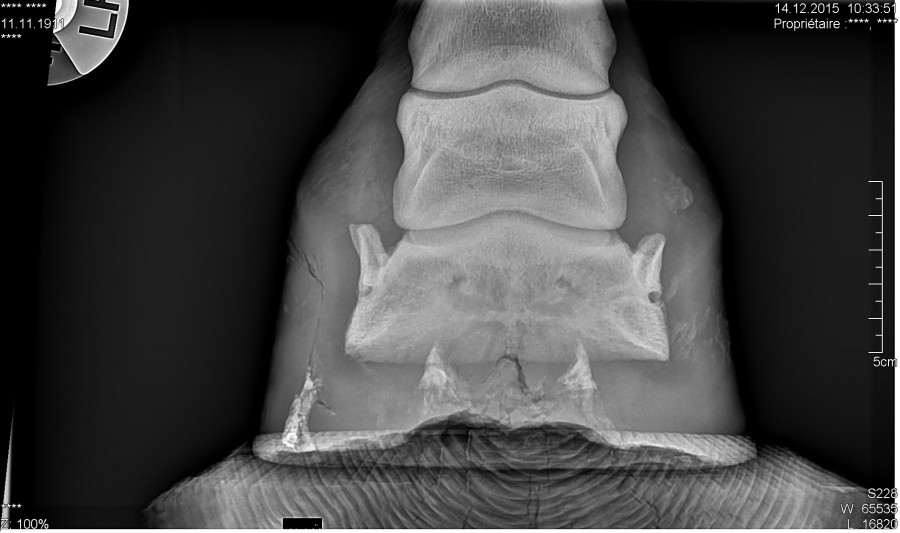

Pour ceux que ça intéresse, les radios :

Alors le verdict .... Une grosse fourmilière qui remontait très haut et qui décollait la paroie, ils ont charcuté tout ça, elle a un gros trou dans la paroie, ça va nécessiter des soins et du temps pour que ça repousse, mais au moins ce n'est pas un problème plus grave et chronique !

Il sonde le pied, qui est clairement la cause de la boiterie selon lui, et décide de faire une radio, malgré cela il n'arrive pas à localiser l'abcès, mais détecte, une petite déformation de la 3 ème phalange, pile à l'endroit ou l'espèce de bosse s'est formée dans la boîte cornée.